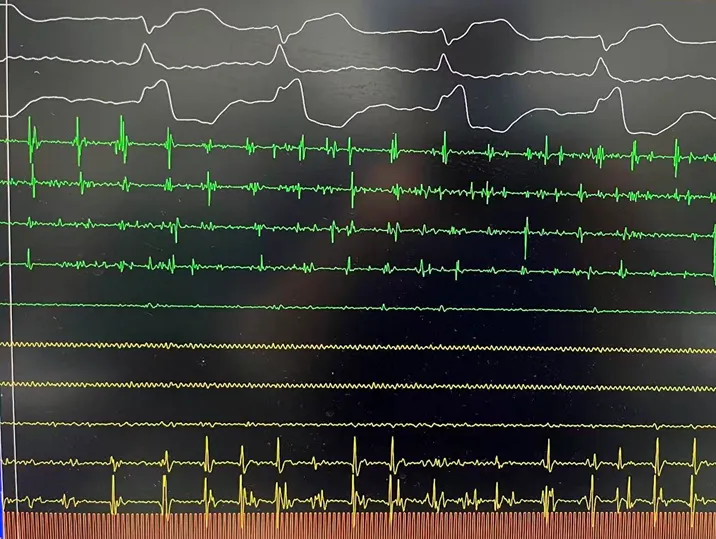

手术在全麻下进行,消融策略涵盖双侧肺静脉、左房后壁及上腔静脉,总计消融73个位点,累计消融时间仅146秒。术中活化凝血时间(ACT)维持在250-300秒,未出现并发症。消融结束后,患者仍为房颤心律,经电复律成功转为窦性心律,手术顺利完成。

RSPV消融及前后电位对比

RIPV消融及前后电位对比

后壁消融及前后电位对比

上腔静脉消融及前后电位对比